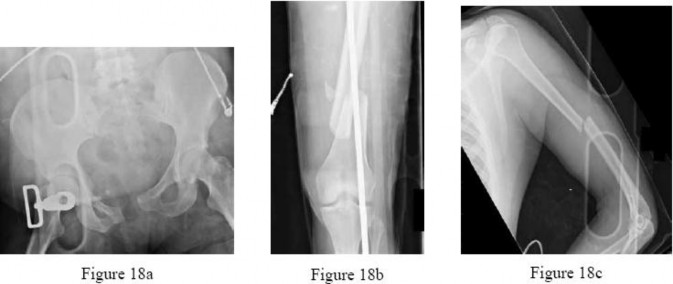

are the radiographs of a 23-year-old man who fell from a height and sustained an isolated injury to his right leg. Which of the following is a useful surgical technique to optimize alignment during intramedullary nailing?